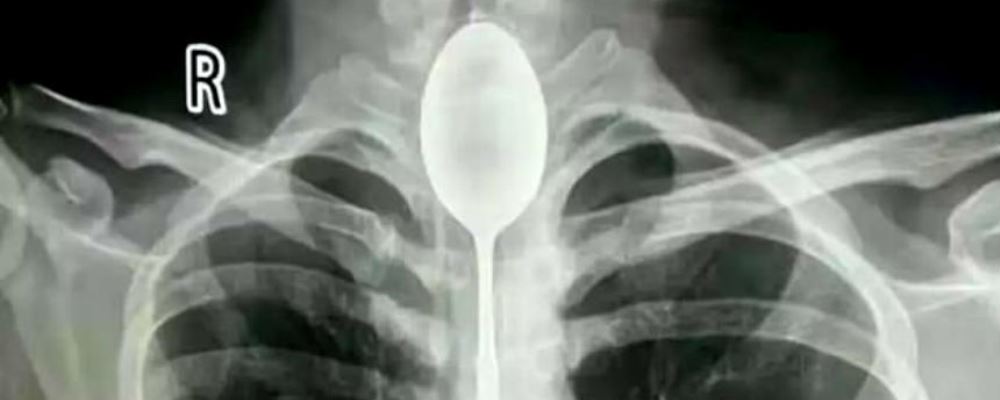

Es lo que ocurrió con un hombre de 26 años que llegó al Hospital General de Xinjiang Meikuang, en China, con una cuchara de 20 centímetros atorada en el esófago. Lo más curioso es que el objeto lo tenía alojado hace un año en su interior, según señala Daily Mail.

«Quedé impactado. Nunca he tenido algo así», dijo Yu Xiwu uno de los médicos que trató al paciente, el cual ya tenía complicaciones en su cuerpo lo que le había provocado una infección en esófago.

Según reconoció el paciente, de apellido Zhang, todo se debió a una apuesta que hizo con unos amigos, donde aseguró que era capaz de tragarse una cuchara. El hombre cumplió su palabra y lo hizo. El problema es que luego no pudo sacársela y anduvo un año con el objeto dentro de su cuerpo.

Afortunadamente los médicos pudieron extraer la cuchara y el hombre se recupera satisfactoriamente.